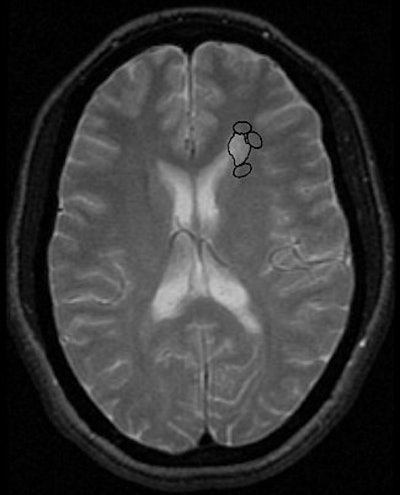

![]() |

| In the same patient, initial image of normal-appearing WM adjacent to this MS plaque, three regions of interest reached 40% fractional anisotropy (FA) reduction threshold and were recorded. Kealey SM, Kim Y, Provenzale JM, "Redefinition of Multiple Sclerosis Plaque Size Using Diffusion Tensor MRI," (AJR 2004;183: 497-503). |

In all, 36 white-matter plaques were examined in the 20 patients. On conventional MRI, the mean plaque area was 60 mm2. The mean plaque FA was 0.251; the mean FA of normal white matter was 0.429 for normal white matter. Applying the 40% FA reduction threshold, the mean combined area of abnormal white matter was 87 mm2 or 145% of the mean plaque area as seen on T2-weighted imaging.